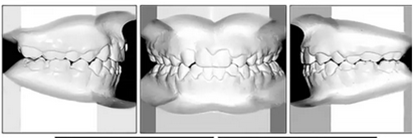

咬合關(guān)系:右側(cè)磨牙有II類關(guān)系傾向,尖牙關(guān)系II類;左側(cè)磨牙關(guān)系完全II類,尖牙關(guān)系I類。上頜雙側(cè)反合,中線稍有偏離。覆合、覆蓋減少。上頜中切牙向腭裂側(cè)旋轉(zhuǎn),上頜右側(cè)尖牙頰側(cè)異位萌出,雙側(cè)乳尖牙仍存在?;颊呱项M弓嚴重擁擠(擁擠度約10mm),下頜弓輕度擁擠4mm(擁擠度約4mm)(圖1 ;圖2)。牙周檢查良好。

總體治療目標已經(jīng)實現(xiàn)。病人的笑容和輪廓有所改善。咬合關(guān)系為I類磨牙關(guān)系,牙列整齊,牙尖交錯關(guān)系良好。反合和中線偏移得以矯正,并實現(xiàn)了正常的覆蓋和覆合。上下牙弓的擁擠問題完全解決,并且完成后全景片顯示良好的牙根傾斜度。疊加顯示良好的縱向和垂直控制(ANB,3.5°; SN / GoMe,42.5°)和矯正上下頜前牙傾斜度(1 / SN,96°; IMPA,87°)(圖10 ; 表)。

治療持續(xù)3年,患者始終保持積極和合作。口腔衛(wèi)生很好。患者和她的父母都對結(jié)果感到滿意。經(jīng)過24個月的保持后,咬合保持得很好(圖11 ; 圖12)。在上牙弓中,應(yīng)用固定舌側(cè)保持器以防止任何復(fù)發(fā)傾向。在下牙弓中,治療后拔除第三磨牙。